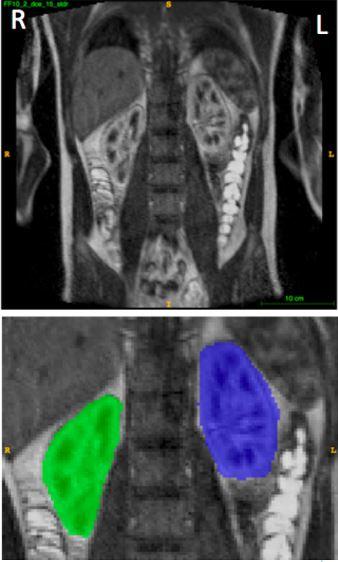

"Vi kom nettopp tilbake fra et møte i Berlin, hvor vi presenterte dataene våre om segmentering av nyrene", forklarer Lundervold. Han snakker om samarbeidspartnere Alexander S. Lundervold og kliniker Jarle Rørvik ved Haukeland universitetssykehus. "Vi brukte bilder fra dynamisk kontrastforbedret magnetisk resonansbilder (DCE-MRI), og anvendt dyp læringsteknologi. Datamaskinen var i stand til å definere hvor nyren var i disse bildene, akkurat som en person ville – ved å analysere grovmorfologi og de fine detaljene til venstre og høyre nyre - på mindre enn fem sekunder.» Senere vil de bruke denne teknologien til å måle filtreringsfunksjonen til pasientens nyrer og assistere i diagnostisering av nyresykdommer.